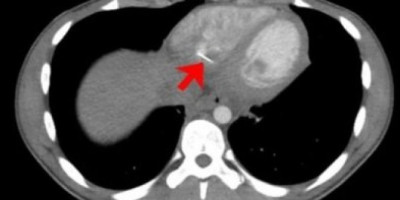

Skeniranjem srca primećen je linearno metalno strane telo u srcu. Predmet je bio oko 3,5 centimetra dugačak i virio je iz donjeg dela desne komore srca, koja pumpa krv u pluća.